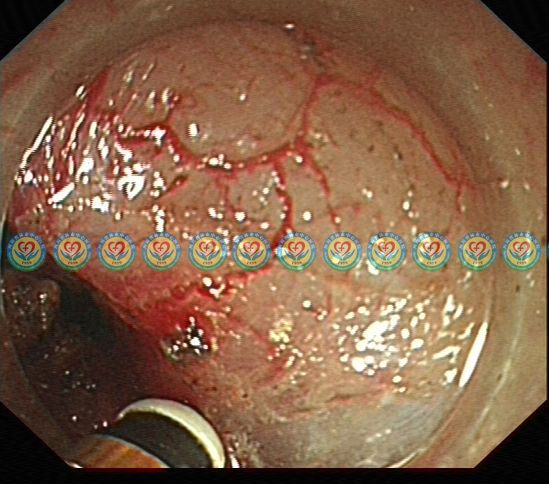

术后3+月复查胃镜,见创面愈合良好